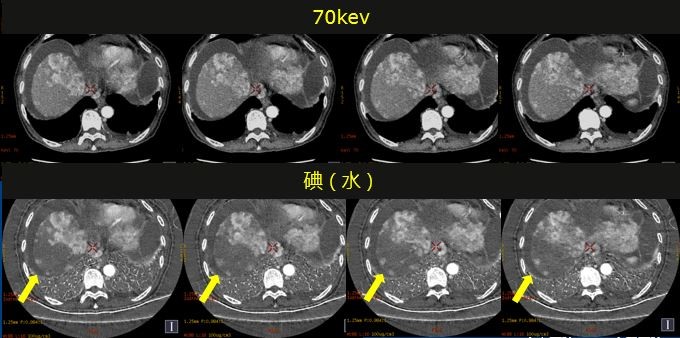

碘基图像对肝脏结节的血供显示更敏感,碘基图上我们可以看到更多、清晰的小病灶。

门静脉显示在60Kev对比度更高,碘基图对含碘的结构显示非常敏感